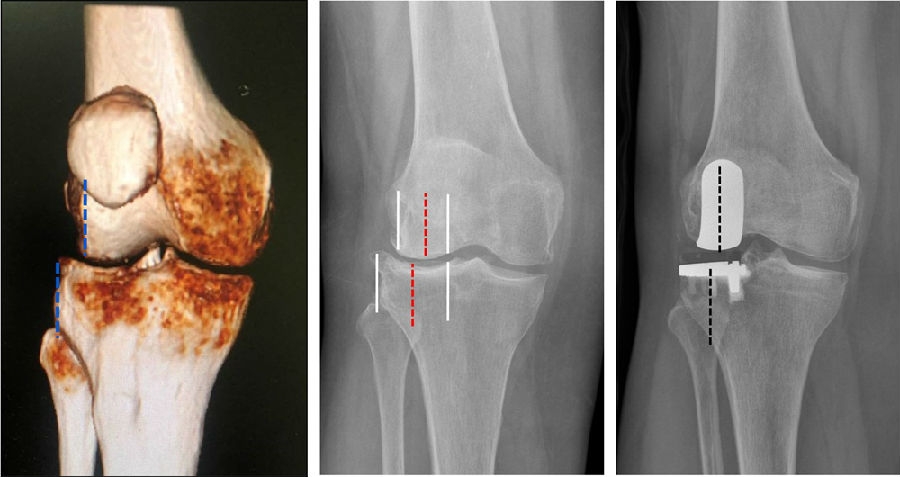

理想假体位置 A.股骨假体 胫骨假体中心线一致;B.股骨假体固定栓与后侧皮质呈35-40°

理想假体位置即前缘平稳过渡,后缘包容很好且不超出。

Case1LUK治疗外侧间室OA

术前

术后